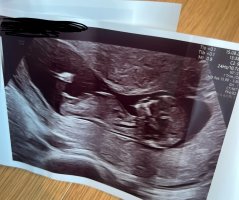

Vil dere gjette ut fra teorien hva kjønnet kan være? blir litt gal og sykehuset ville ikke si det fordi det var for tidlig..

nå har jeg fått bekreftet om at det er liten jenteHar disse ogsåhåper man kan se det på et av bildene hvertfall (alle de er tatt samme dag 12+3) @lyse gul